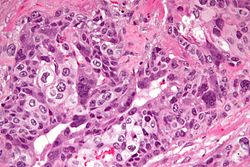

| Embryonal carcinoma | prominent nucleoli, vescicular nuclei | var. arch.: tubulopapillary, glandular, solid, embryoid bodies (ball of cells in surrounded by empty space on three sides), +/-nuclear overlap, mitoses common | CD30 | usu. part of a mixed GCT | |